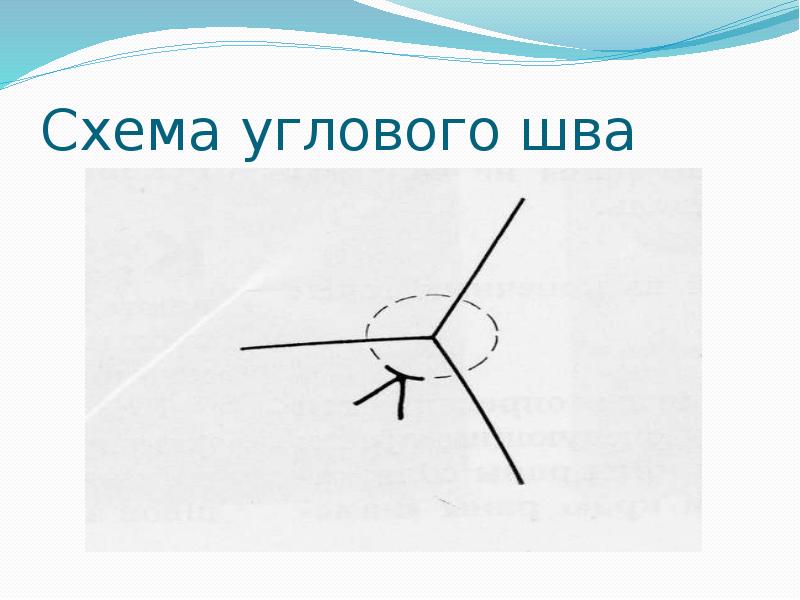

- 45. Схема углового шва